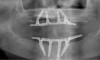

Fig 2. Four vertical machined-surface osseointegrated implants placed in 1983 penetrated the inferior cortex up to 3 mm to 4 mm in depth, immediate postoperative.

Figure 2

Fig 3. At 4 years and 5 months follow-up, reparative bone had formed to the apices of all implants.

Figure 3

The Toronto Conference in 1982, chaired by Professor George Zarb and presented by Professor Per-Ingvar Brånemark, was a seminal event that changed edentulous treatment planning concepts irrevocably. No longer was it necessary to rebuild lost bone through grafting alone in either arch. The severely atrophic mandible, for example, could be treated with as few as four implants used to support a bone-sparing prosthesis through integrated tooth analogs, as demonstrated in Figure 1 through Figure 3. Here, an 81-year-old patient presented with severe mandibular atrophy (Figure 1) from denture wear since a very young age and had a history of being unable to manage a mandibular prosthesis despite numerous attempts at new denture construction. Four vertical machined-surface osseointegrated implants were placed in 1983 by Professor Brånemark, and all four penetrated the inferior cortex up to 3 mm to 4 mm in depth, as shown on the immediate postoperative panoramic film (Figure 2). At 4 years and 5 months, reparative bone had formed to the apices of all implants (Figure 3), and all of them remained in uncompromised function until the patient passed away at age 90.